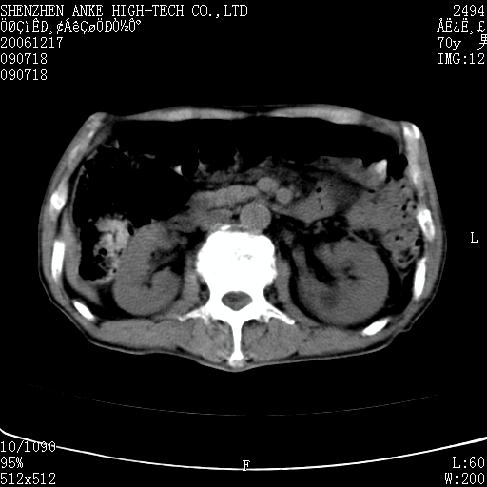

患者:男,70岁,腹部疼痛待查.b超见左肾脏占位待排.因为患者经济条件不好,没有做增强.

支持胰腺癌伴肝转移;左肾囊肿?

胰尾与左肾上缘部位见有一肿块影,密度不均匀,周围边界不清晰,与胰腺相连,与左肾边界不清,肝脏内见有多发低密度影,考虑胰尾癌伴左肾侵犯并肝内转移。最好是做个增强。

考虑:1,胰腺癌伴肝转移;2,左肾小囊肿。

与胃、脾及左肾之间见一巨大肿块影,其内密度不均,边界欠清,与胰腺关系密切。肝实质内见多个类圆形低密度灶,边界较清。符合胰腺癌并肝转移表现。

考虑:1,胰腺癌伴肝转移;2,左肾小囊肿. 3胰腺病变与左肾分界不清,肾脏可能受累。

与胃、脾及左肾之间见一巨大肿块影,其内密度不均,边界欠清,与胰腺关系密切。肝实质内见多个类圆形低密度灶,边界较清。符合胰腺癌并肝转移表现。

同意胰尾部癌累及左肾前,肝多发转移,左肾小囊肿。

胰尾与左肾上缘部位见有一肿块影,密度不均匀,周围边界不清晰,与胰腺相连,与左肾边界不清,肝脏内见有多发低密度影,考虑胰尾癌伴左肾侵犯并肝内转移。最好是做个增强。